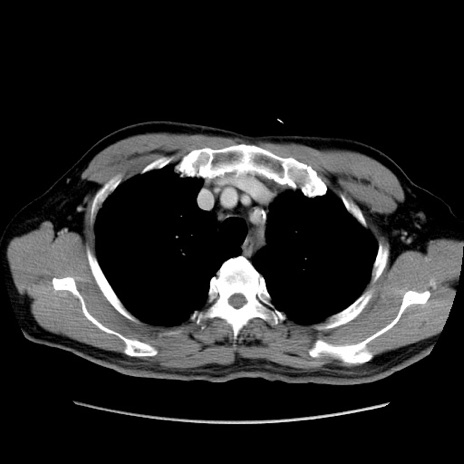

冠状断像